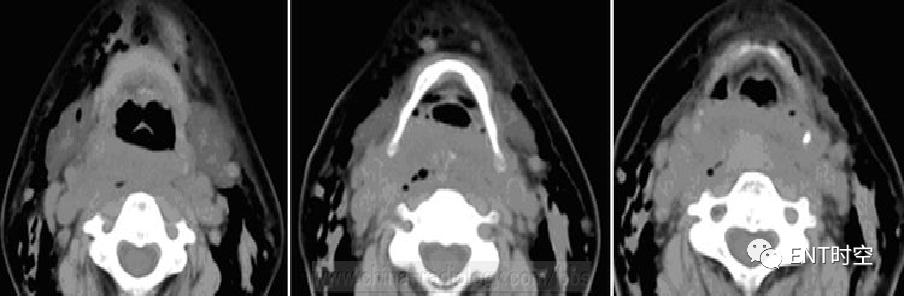

女性,54岁,误食猪骨头3日、加重伴颈部肿痛2天。

平扫示咽喉后间隙及椎前间隙增、可见弥漫性肿胀影,病变区边界欠清,肿胀区内可见多发点状气体影。病变范围累及双侧咽旁软组织。矢状重建示咽后壁明显增厚。

咽后壁脓肿手术后确诊患者皮下气肿范围为上至双侧颌下区,下至胸骨下平面,双侧至锁骨中线。全麻成功后支撑喉镜下见白色梭形猪骨横行卡于左侧梨状窝处。